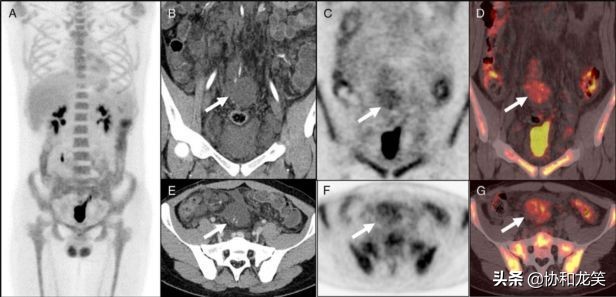

临床为除外恶性病变行18F-FDG PET/CT检查,结果提示患者腹膜后及双侧腹股沟病灶轻度放射性摄取增高,SUVmax为3.7;骨髓弥漫放射性摄取增高,SUVmax为4.6,可能与患者贫血有关;上述结果不支持典型的软组织恶性肿瘤推论。

图A,骨髓弥漫摄取FDG,SUVmax为4.6。

图B-G白色箭头所示,腹膜后软组织肿物轻度摄取FDG,SUVmax为3.7。